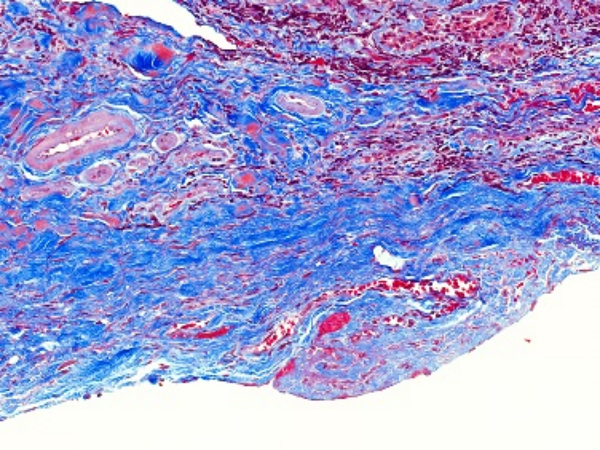

Masson染色是一种用于显示组织中纤维成分的特殊染色方法,主要用于区分胶原纤维和肌纤维,在病理学和组织学研究中有广泛的应用。**一、染色原理**1. 试剂作用 - **酸性复红**:它是一种酸性染料,能够将细胞质、肌纤维等染成红色。在染色过程中,酸性复红与肌纤维中的碱性蛋白结合,使肌纤维呈现出红

19033981702 立即咨询Masson染色是一种用于显示组织中纤维成分的特殊染色方法,主要用于区分胶原纤维和肌纤维,在病理学和组织学研究中有广泛的应用。

**四、结果观察与分析**

1. 细胞核

- 经过Weigert铁苏木精染液染色后,细胞核呈现黑色。可以观察细胞核的大小、形状、位置以及核内结构(如核仁),这有助于判断细胞的类型和状态。

2. 肌纤维

- 被酸性复红染色后呈红色,通过观察肌纤维的分布、走向和形态,可以了解肌肉组织的结构和功能。例如,在心肌组织中,心肌纤维呈分支状,相互连接成网状;在平滑肌组织中,肌纤维呈长梭形,排列较为规则。

3. 胶原纤维

- 被苯胺蓝染色后呈蓝色。可以观察胶原纤维在组织中的分布和含量,这对于研究组织的纤维化程度、创伤修复等过程具有重要意义。例如,在肝脏纤维化的组织中,会出现大量蓝色的胶原纤维增生。